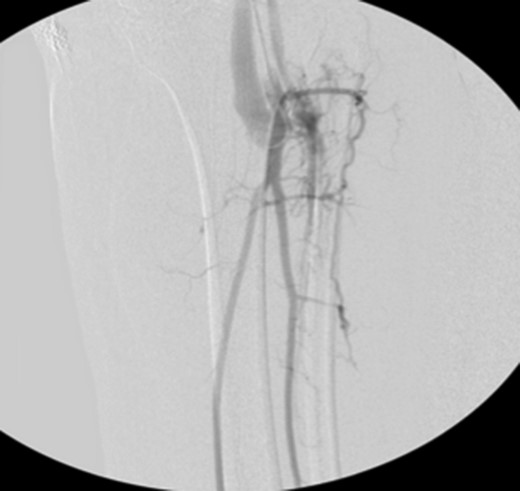

Patient underwent a left lower extremity angiogram. During the procedure she was found to have patent aorta and bilateral common iliac artery. There was no disease visualized in the left external iliac artery, common femoral artery (CFA), SFA, patent previously placed stent, patent above and below the knee PA and two vessel run off to the foot (Fig. 1). Upon delayed fluoroscopic images we identified contrast filling the deep venous system rather quickly suggesting a high volume fistula (Fig. 2). We then identified the fistula between ATA and ATV. Although ATA was previously ligated there was retrograde filling of the artery from unnamed branches, which communicated with the venous system as shown in. In the midcalf (ATA) was cannulated with a micropuncture needle. Micropuncture wire was inserted and a 5-Fr sheath was inserted after exchanging over wire. At this point VortX coils (Boston Scientific) were placed from the curve of ATA until the whole AVF was sealed. Anterograde angiogram showed no flow through the fistula (Figs 3 and 4). There was a palpable PT and DP pulse at the completion of the procedure. Sheath was removed, pressure dressing applied. Patient was discharged home same day. Recovery has been unremarkable. Three months follow-up claudication symptoms have significantly improved.

Anterograde angiogram showed no flow through the fistula tract with two vessels run off.